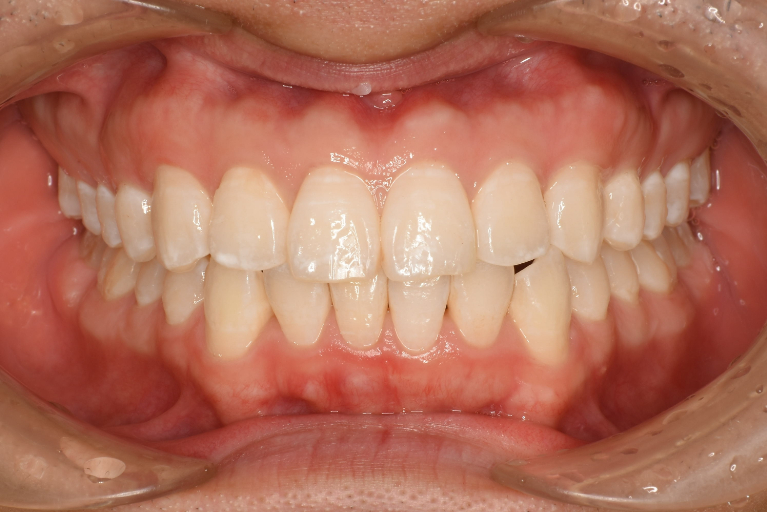

術前

術後

| 治療名 | インビザライン・ライト |

| 治療説明 | インビザラインを用いたマウスピース矯正により歯並びとかみ合わせの治療を行い、見た目と清掃性を改善しました。 |

| 治療回数・期間 | 4ヶ月 |

| 副作用とリスク | 矯正用マウスピースを20時間/1日装着して頂く必要があります。治療中は歯の移動による痛み、咬合時痛が生じることがあります。矯正治療により歯肉退縮、歯根吸収が起こるおそれがあります。マウスピースの数に限りがあるため適応できない場合があります。 |

| 料金(税込) | 治療計画作成料:55,000円 インビザライン矯正治療費:660,000円 リテーナー:55,000円 総額:770,000円 |